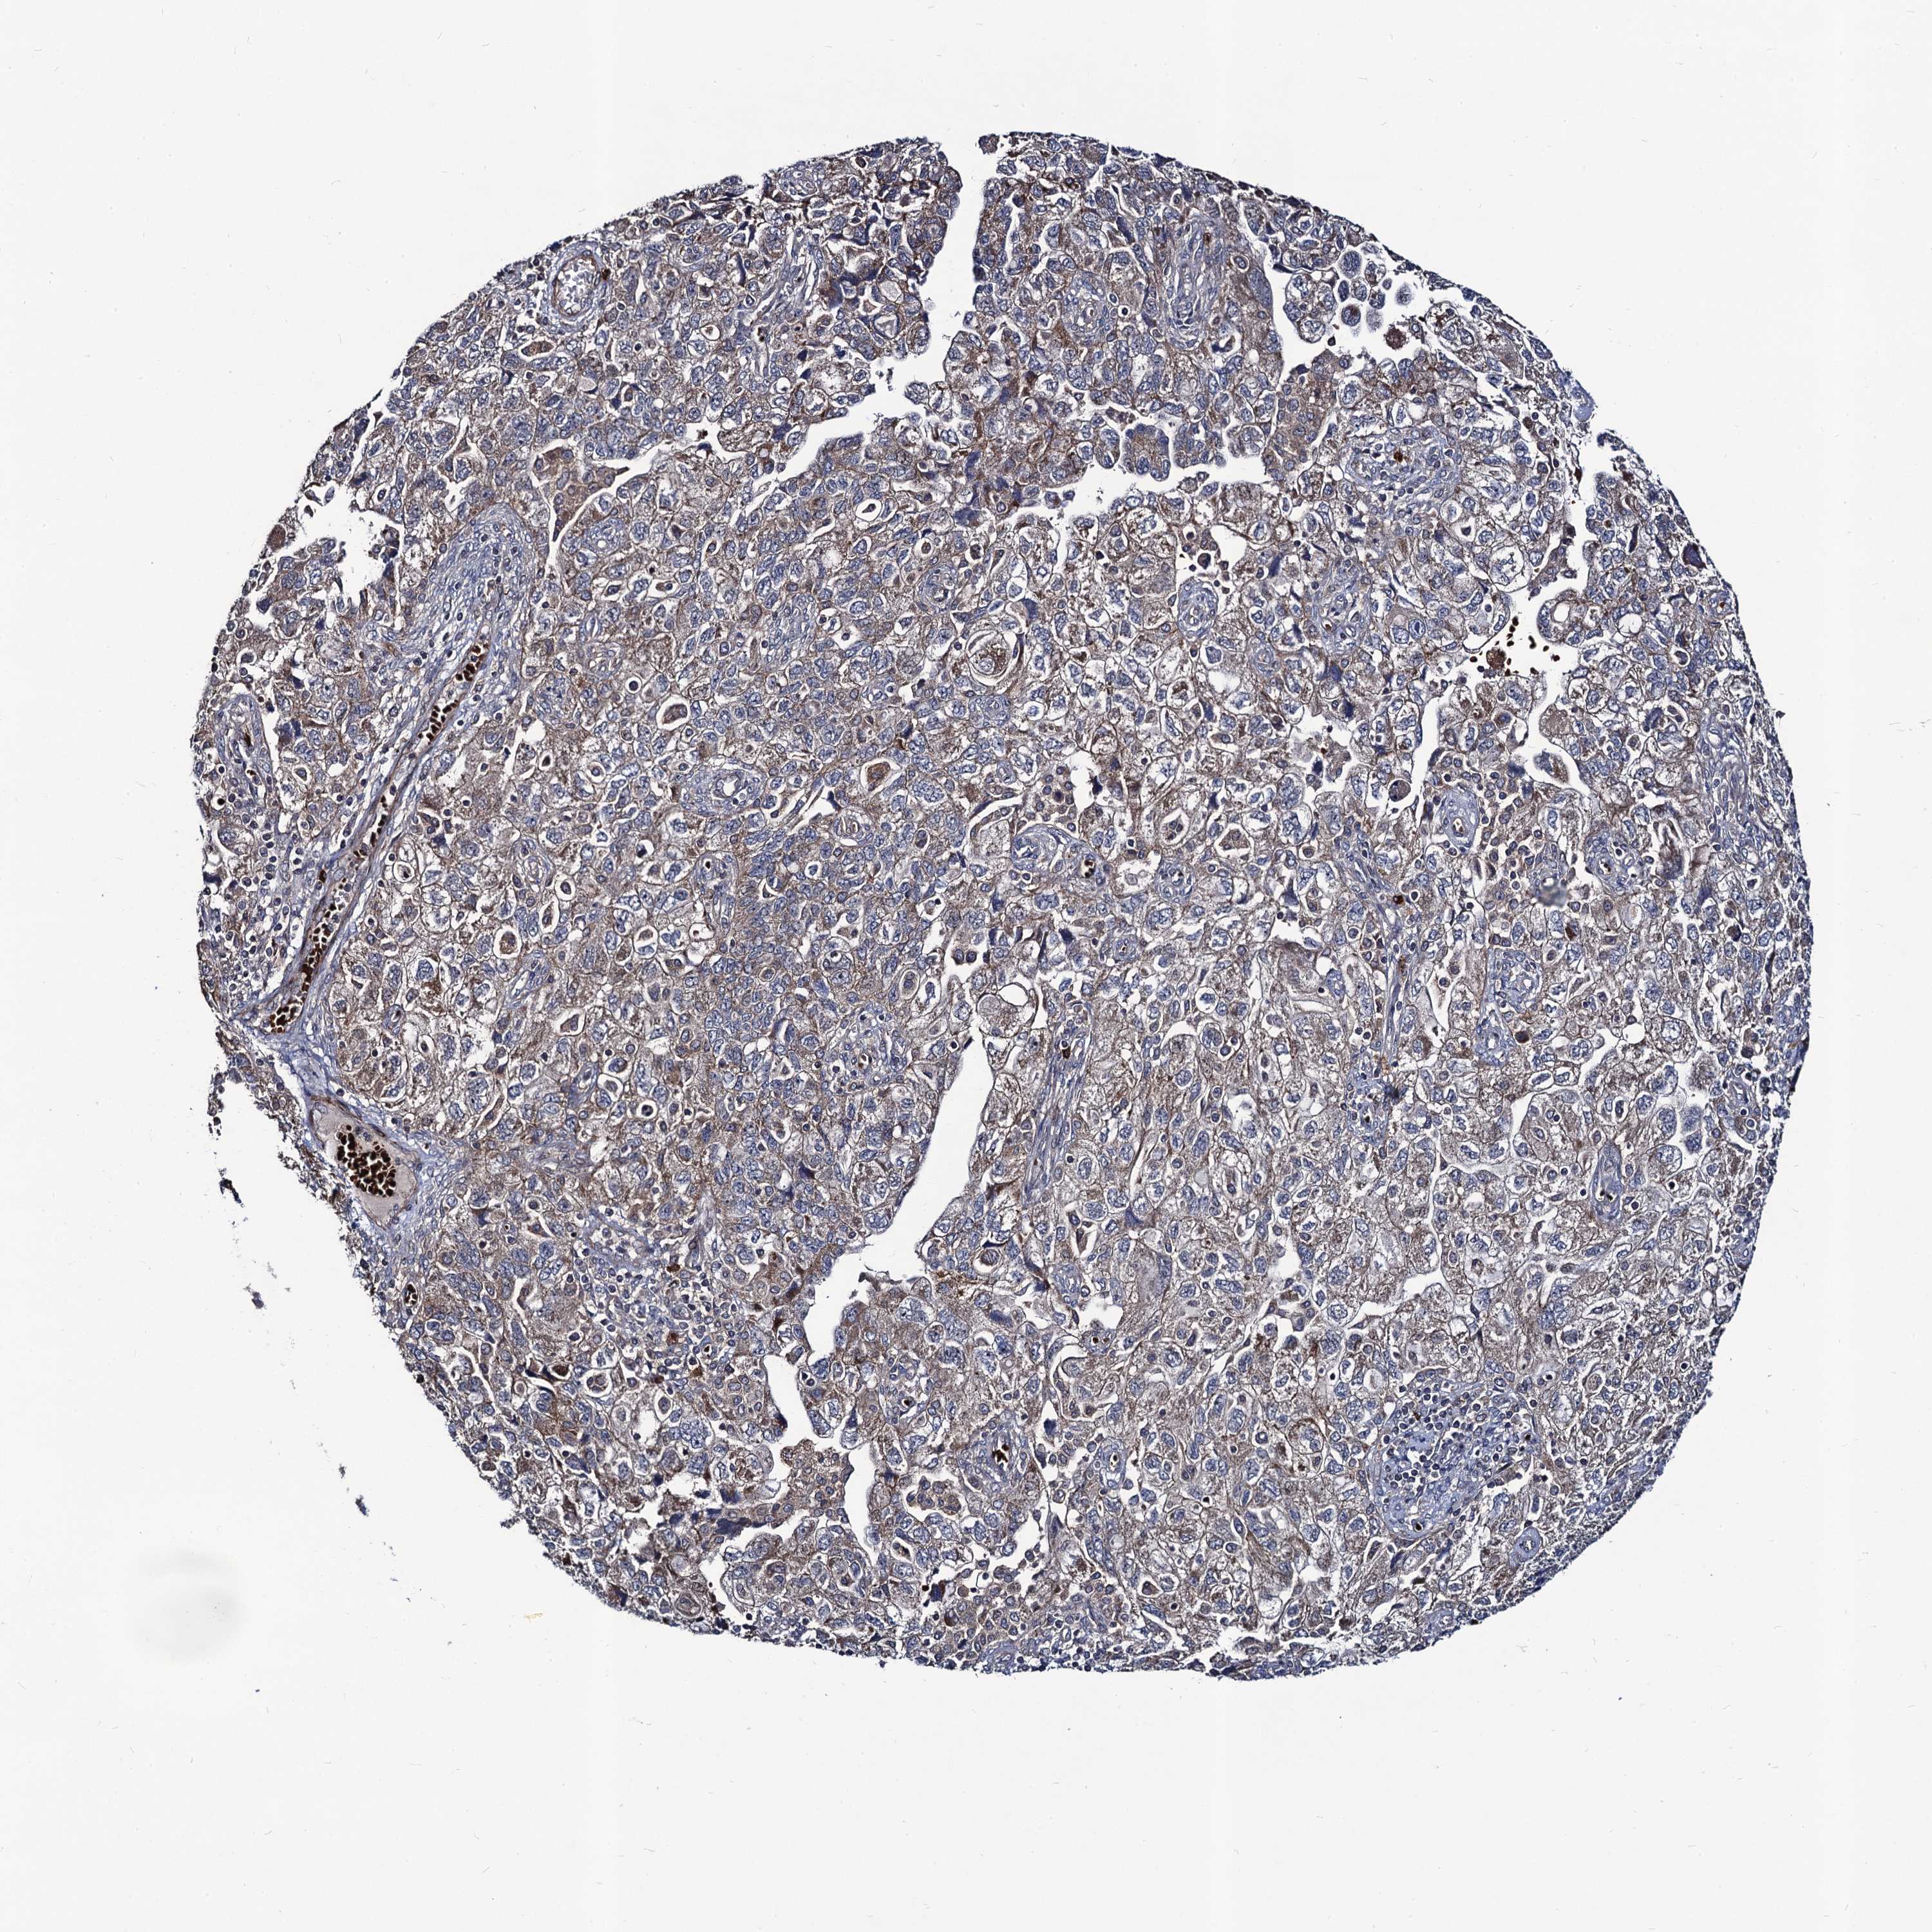

OVARIAN CANCER - Protein expressioni

A mouse-over function shows sample information and annotation data. Click on an image to view it in a full screen mode. Samples can be filtered based on level of antibody staining by selecting one or several of the following categories: high, medium, low and not detected. The assay and annotation is described here.

Note that samples used for immunohistochemistry by the Human Protein Atlas do not correspond to samples in the TCGA dataset.

Antibody stainingi

Antibody staining in the annotated cell types in the current human tissue is reported as not detected, low, medium, or high, based on conventional immunohistochemistry profiling in selected tissues. This score is based on the combination of the staining intensity and fraction of stained cells.

Each image is clickable and will lead to virtual microscopy that enables deeper exploration of all samples and also displays staining intensity scores, fraction scores and subcellular localization as well as patient and tissue information for each sample.

Antibody HPA041507

Antibody HPA041599

Cystadenocarcinoma, serous, NOS

Carcinoma, endometroid

Cystadenocarcinoma, mucinous, NOS

Carcinoma, NOS